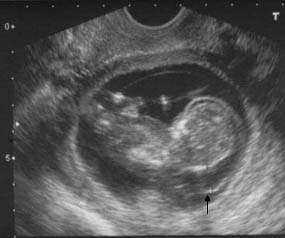

Jakarta - Tahukah Anda? Sebelum lahir ke dunia nyata, anak-anak zaman sekarang sudah lebih dulu eksis di dunia maya. Hal ini sudah lumrah terjadi mengingat banyak para orangtua saat ini yang gemar mendokumentasikan kehidupan mereka, termasuk foto bayi dalam rahim di situs jejaring sosial.

AVG menyurvei para ibu di sembilan negara yakni, Amerika Serikat (AS), Kanada, Inggris, Prancis, Italia, Spanyol, Jepang, Australia dan Selandia Baru. Dari survei itu, ditemukan bahwa hampir seperempat anak di negara-negara itu telah memulai kehidupan digital sebelum lahir ke dunia. Ditandai dengan saat dimana orangtua mereka mengunggah scan foto sonogram pra kelahiran di jejaring sosial.